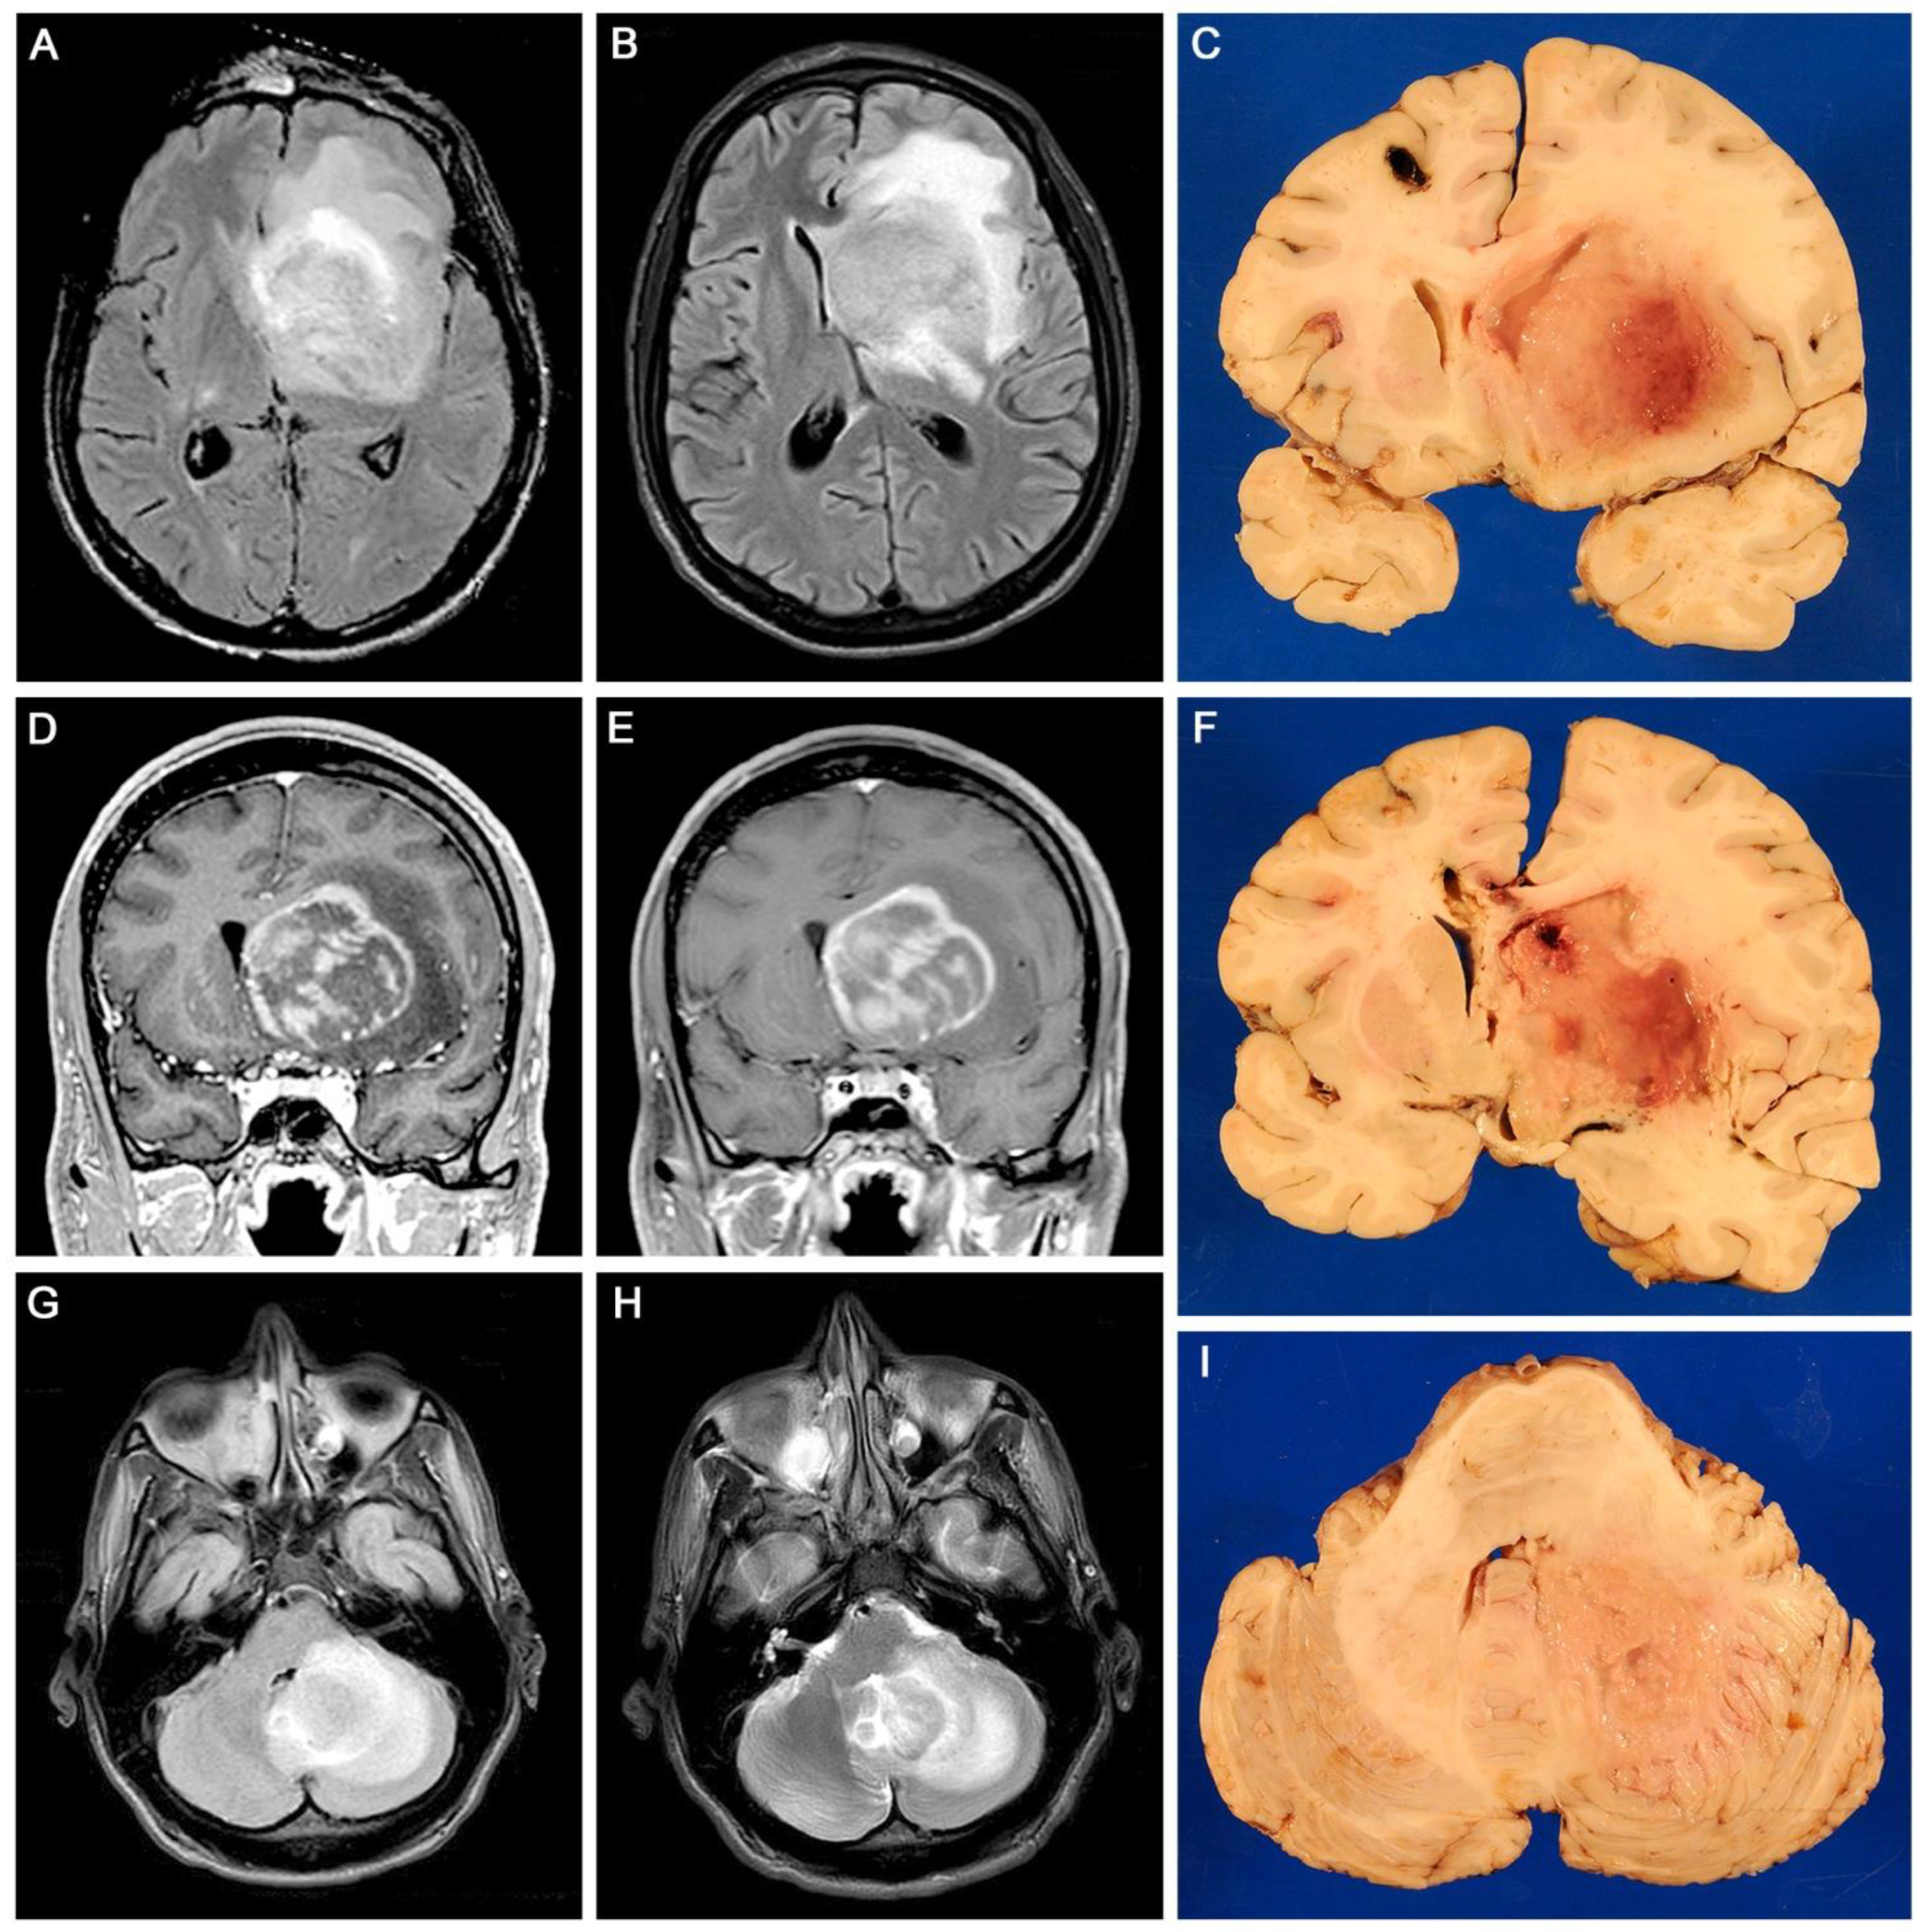

Gross examination of coronal sections of the brain revealed a large mass of irregular, poorly defined edges located in the right basal ganglia, which measured 5 × 5 × 4 cm, and extended rostrally and medially into the corpus callosum and caudally into the parietal lobe. This mass was homogeneous, grey, and of soft, granular consistency. It caused significant edema, which produced the partial compression of the lateral ventricle and subfalcine herniation of the cingulate gyrus. A second lesion of similar characteristics was found in the left frontal lobe, measuring 3 × 2 cm, in which the tract of the surgically implanted drain was found. A third mass, also homogeneous, grey and soft, and of poorly defined edges, measured 3 × 2.5 cm and was found in the right cerebellar hemisphere. Figure 1 depicts the neuroimaging and gross aspects of the tumors.

Figure 1.

Neuroimaging and neuropathology: Axial plane MRI shows a large mass in the right basal ganglia which causes significant edema (Panels (A,B)). Coronal MRI shows the mas is ring enhancing (Panels (D,E)). Coronal sections of the brain corroborated a large mass of poorly defined edges with prominent areas of necrosis, located in the right basal ganglia with areas of necrosis, that causes significant edema and compresses the lateral ventricle; the site of the surgical probe can be seen on the contralateral frontal lobe (Panels (A–F)). Another similar homogeneous mass can be seen in the right cerebellar hemisphere, causing a prominent midline shift (Panels (G–I)).